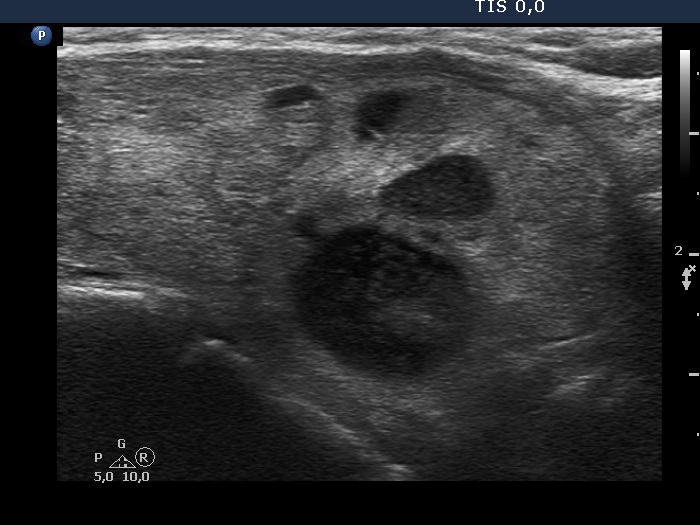

The borders of the nodule - case 2152 (ultrasonographic picture 8)

Lower part of the left lobe, longitudinal scan.